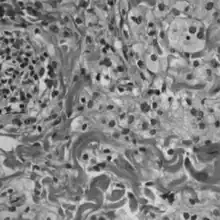

Histologically, ECD differs from Langerhans cell histiocytosis (LCH) in a number of ways. Unlike LCH, ECD does not stain positive for S-100 proteins or Group 1 CD1a glycoproteins, and electron microscopy of cell cytoplasm does not disclose Birbeck granules.[6] Tissue samples show xanthomatous or xanthogranulomatous infiltration by lipid-laden or foamy histiocytes, and are usually surrounded by fibrosis. Bone biopsy is said to offer the greatest likelihood of reaching a diagnosis. It would appear that approximately half these patients harbor point mutations of the BRAF gene at codon 600 substituting the amino acid glutamine for valine. In some, there is histiocyte proliferation, and on staining, the section is CD68+ and CD1a-.